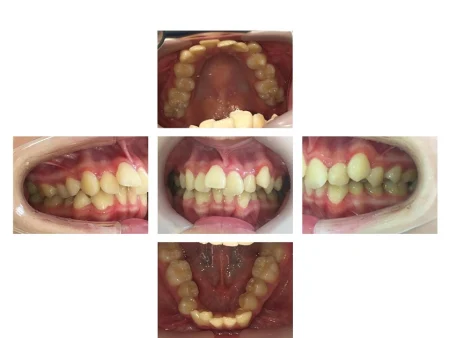

拝見したところ、歯並びの幅が狭くスペースが不足していることにより、全体的に歯が重なり合って並んでいる「叢生(そうせい)」でした。

また、上の歯並びが前方に出ている「上顎前突(じょうがくぜんとつ)」も見られ、唇が閉じにくく口呼吸が増えていました。

口呼吸で口の中が乾燥することにより細菌が増え、歯ぐきの炎症も起こっていました。